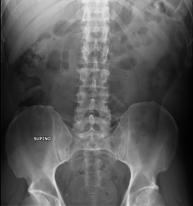

- RX Abdomen

Tècnica que usa els raigs X a través de la qual s'obtenen imatges de l'abdomen (estómac, intestí prim, intestí gros, fetge, ronyons, bufeta, pelvis òssia, etc.) per al seu estudi. - RX Columna lumbar

Procediment que permet, mitjançant l'ús de raigs X, i després d'injectar un contrast a l'interior de l'articulació, detectar lesions d'aquestes articulacions (cartílag, os, tendons, etc. ) segons la distribució del contrast. - RX Pelvis

Procediment que usa els raigs X a través de la qual s'obtenen imatges de la pelvis per al seu estudi, especialment dels ossos pèlvics. - RX Edat òssia